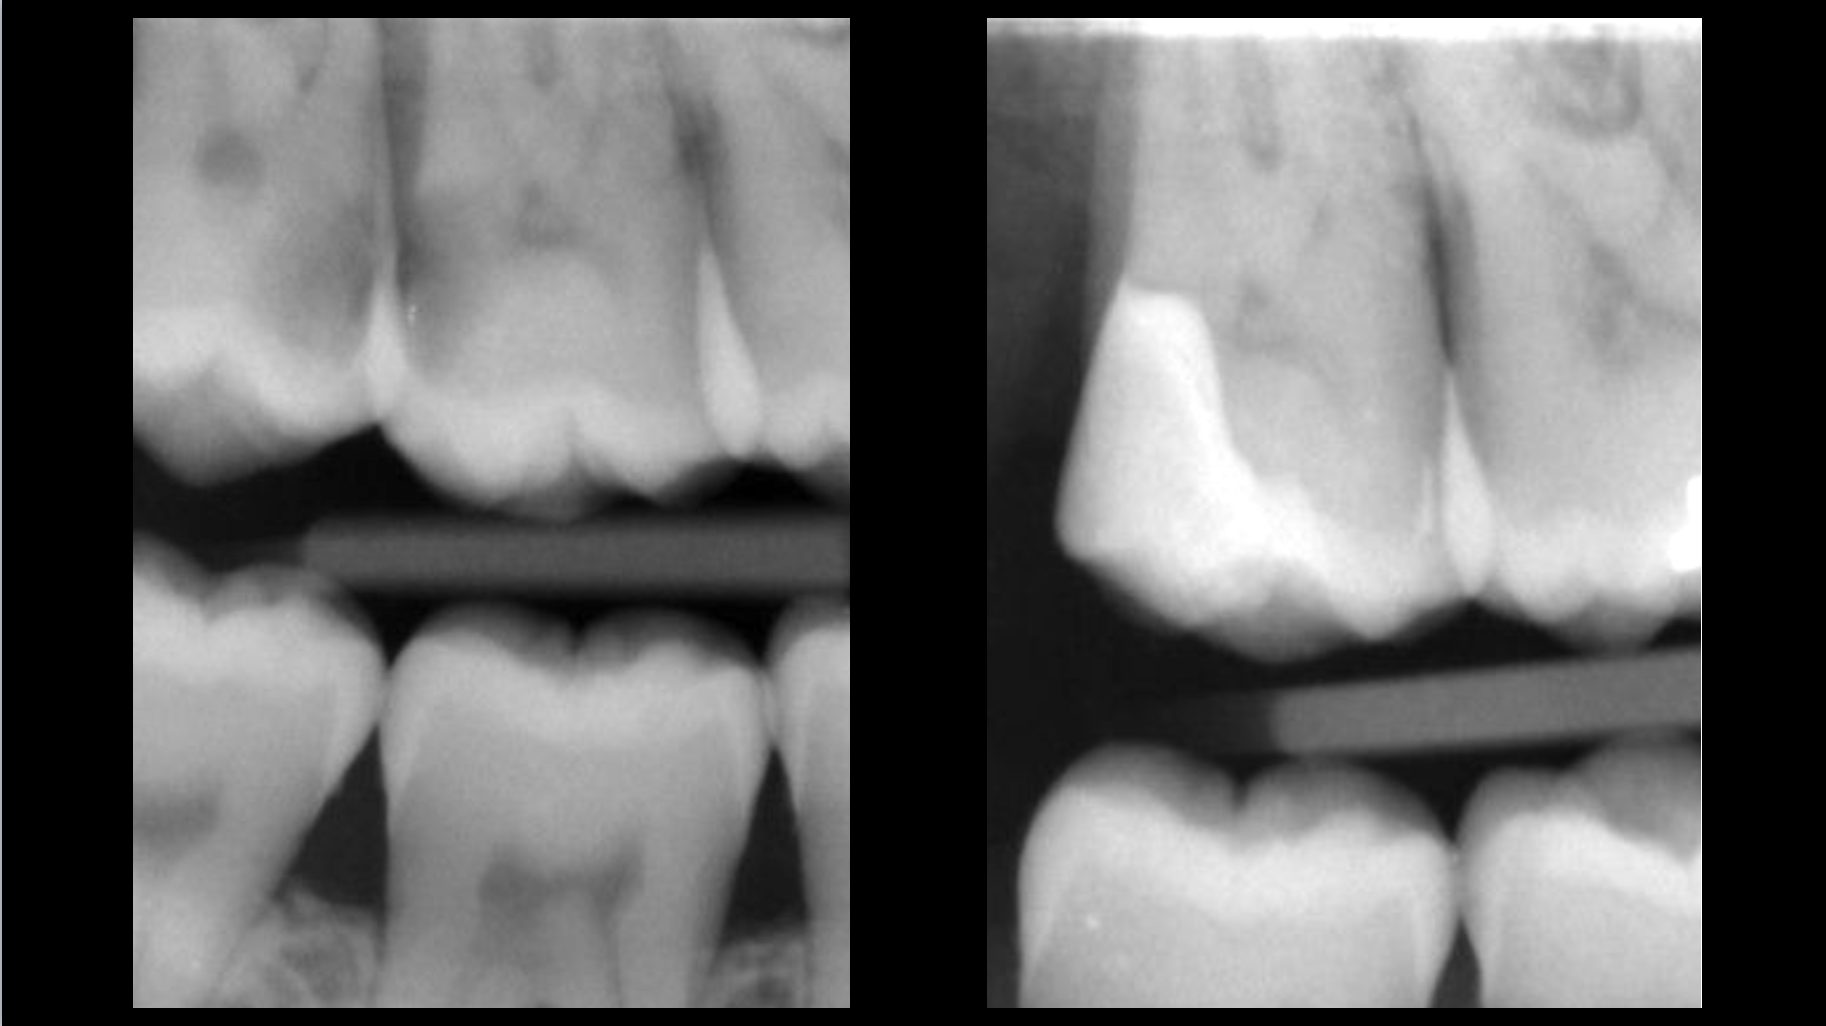

- An intra-canal infection is present despite the existing root canal treatment and is causing an apical lesion.

Clinical case

Root canal retreatment: 80–95% success rate